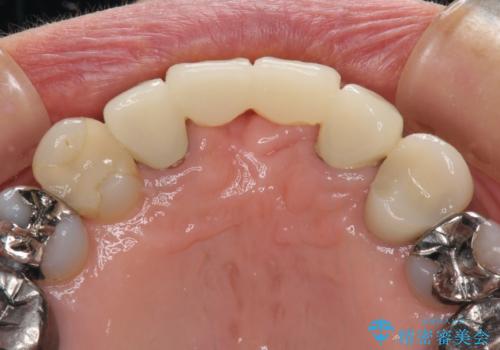

仮歯自体はとても綺麗でしたが、2本の歯が欠損している部分に上唇小帯が入り込んでいたため、歯肉形成を行った上で仮歯を調整し、オールセラミックブリッジを装着することとしました。

上唇小帯を切除したことで、ブリッジのダミー部分に触れて腫れていた歯肉は健全な状態になりました。